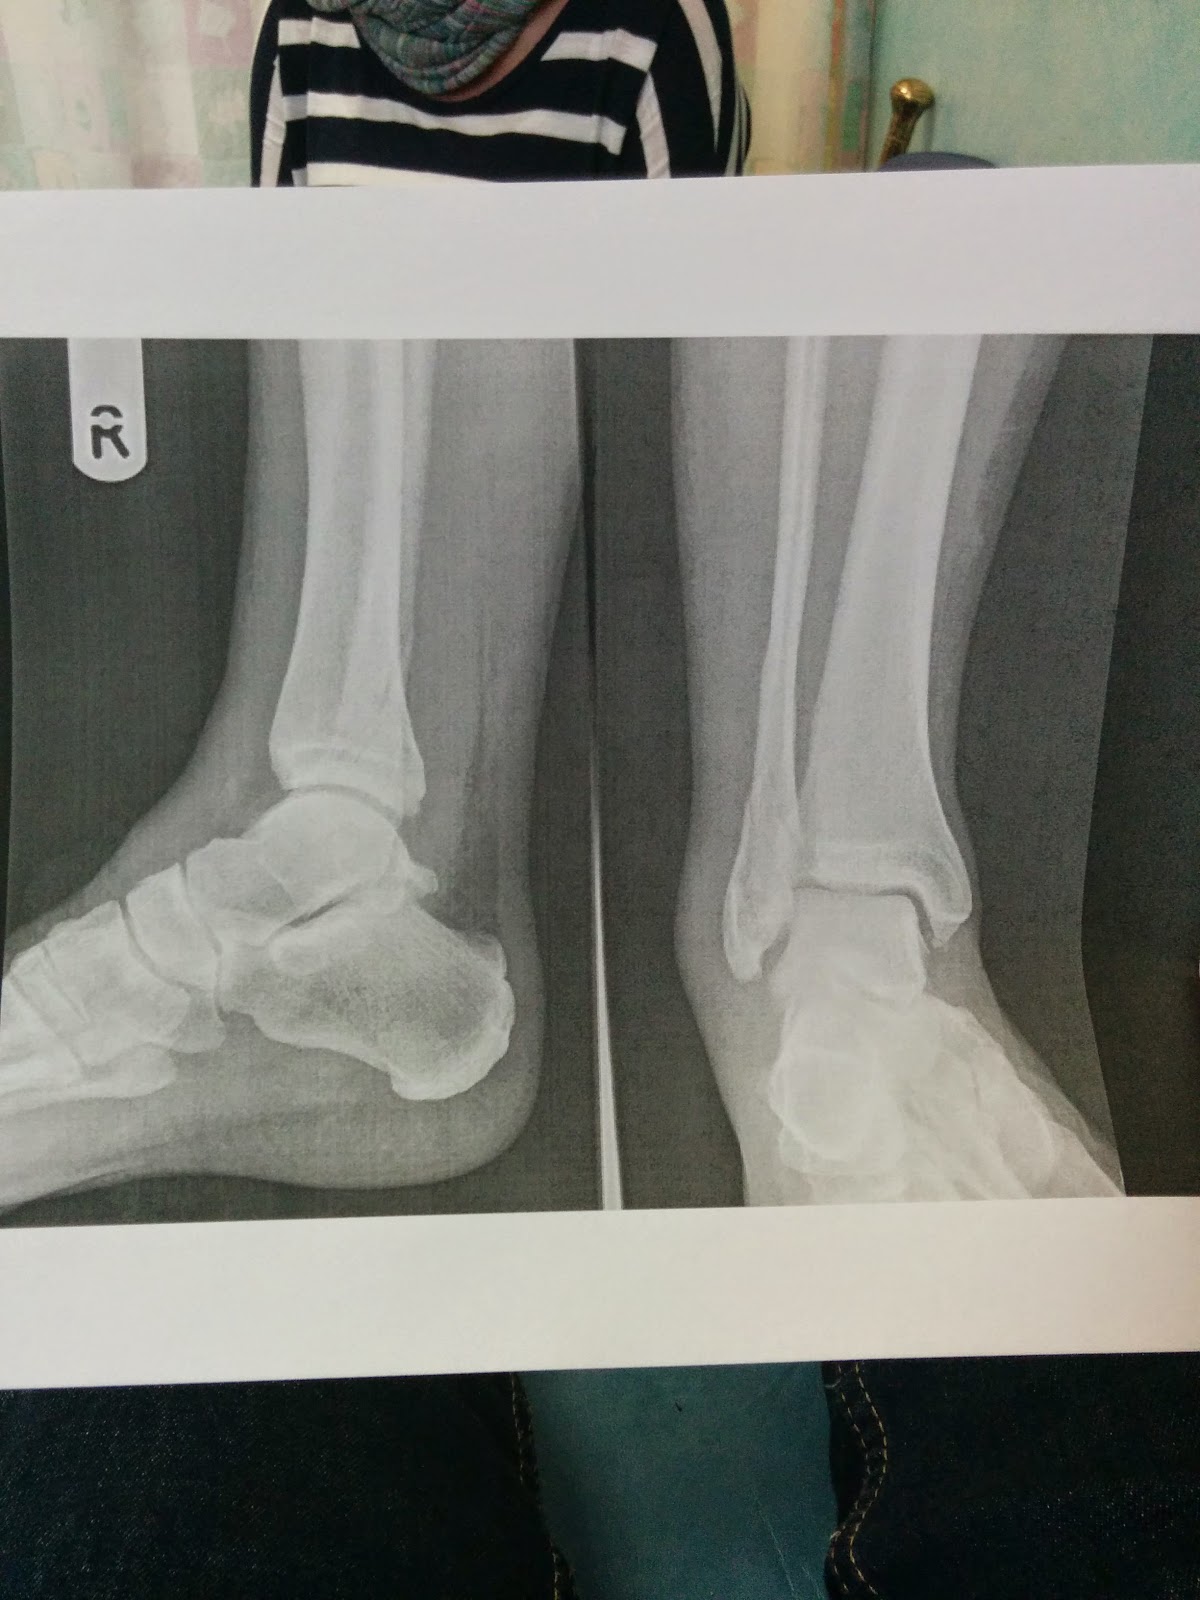

After the walk Tor and I went on a big swing and I had a bad break and broke my ankle. Problem was I didn’t realise it until later when Angie took me to the hospital.